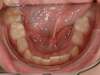

Encombrement aux deux arcades.Traitement par gouttières.

Avant

Après